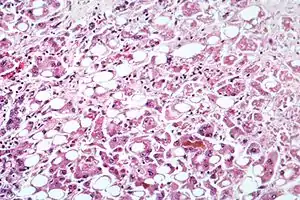

| Alcoholic hepatitis as seen with a microscope, showing fatty changes (white circles), remnants of dead liver cells, and Mallory bodies (twisted-rope shaped inclusions within some liver cells). (H&E stain) | |

Steatohepatitis is seen in both alcoholic and non-alcoholic liver disease and is the culmination of a cascade of events that began with injury. In the case of non-alcoholic steatohepatitis, this cascade is initiated by changes in metabolism associated with obesity, insulin resistance, and lipid dysregulation.[57][58] In alcoholic hepatitis, chronic excess alcohol use is the culprit.[59] Though the inciting event may differ, the progression of events is similar and begins with accumulation of free fatty acids (FFA) and their breakdown products in the liver cells in a process called steatosis.[57][58][59] This initially reversible process overwhelms the hepatocyte's ability to maintain lipid homeostasis leading to a toxic effect as fat molecules accumulate and are broken down in the setting of an oxidative stress response.[57][58][59] Over time, this abnormal lipid deposition triggers the immune system via toll-like receptor 4 (TLR4) resulting in the production of inflammatory cytokines such as TNF that cause liver cell injury and death.[57][58][59] These events mark the transition to steatohepatitis and in the setting of chronic injury, fibrosis eventually develops setting up events that lead to cirrhosis and hepatocellular carcinoma.[57] Microscopically, changes that can be seen include steatosis with large and swollen hepatocytes (ballooning), evidence of cellular injury and cell death (apoptosis, necrosis), evidence of inflammation in particular in zone 3 of the liver, variable degrees of fibrosis and Mallory bodies.[57][60][61]